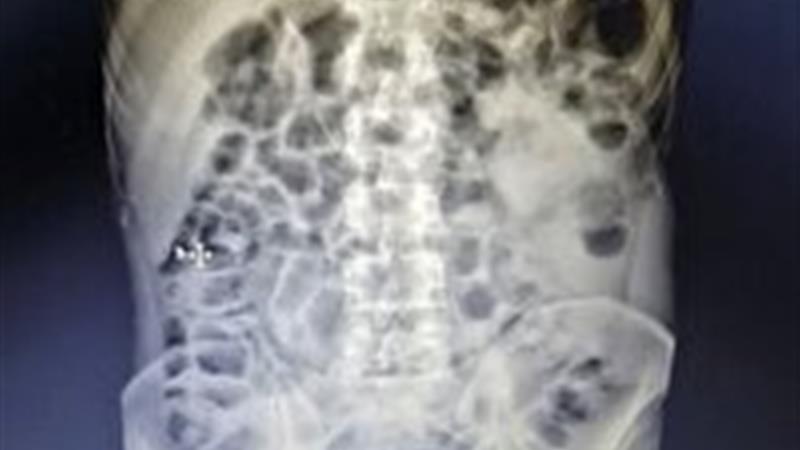

به گزارش خبرگزاری صداو سیما مرکز یزد و به نقل از روابط عمومی بیمارستان ضیایی اردکان، پس از تصویربرداری از بیمار مشخص شد قطعه فلزی شکسته و تیز از دوازدهه عبور کرده و در روده گیر کرده است؛ وضعیتی که معمولاً نیازمند اعزام فوری و جراحی باز است.